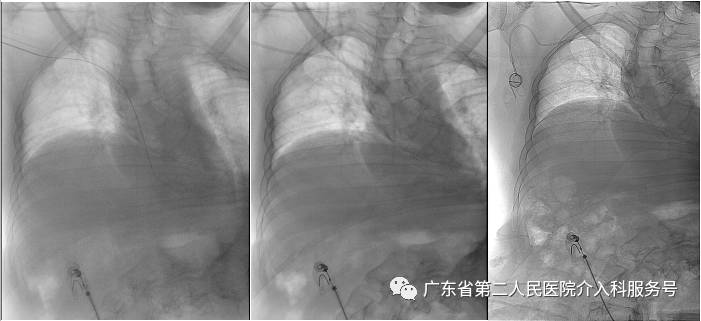

C.建好皮下隧道时,可透视调整导管远端在下腔静脉内的深度(常为T5~T7之间)

D.埋好输液港(红圈内)后,可透视了解和捋顺导管,防止导管打折,以及导管远端在下腔静脉内的深度(常为T5~T7之间)